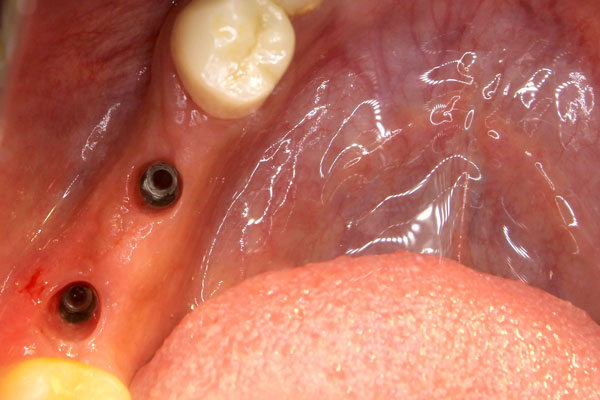

Screw Retained Dental Implant Crowns

Screw Retained Dental Implant Crowns

Screw Retained Dental Implant Crowns

Screw Retained Dental Implant Crowns

Screw Retained Dental Implant Crowns

Screw Retained Dental Implant Crowns

Screw Retained Dental Implant Crowns

Screw Retained Dental Implant Crowns